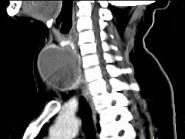

问题 女,56岁,发现颈部肿块1月余,CT如图所示,最可能诊断为()

选项 A.甲状舌管囊肿 B.甲状腺乳头状癌 C.甲状腺原发淋巴瘤 D.甲状腺腺瘤 E.甲状腺脓肿

答案 D